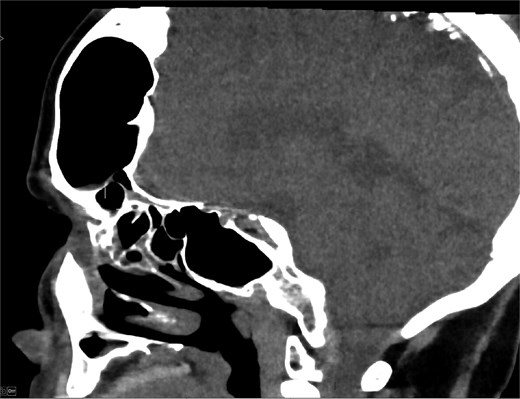

MRI demonstrated marked expansion of the left frontal sinus, consistent with PD, exerting a mass effect on the adjacent left frontal lobe and associated with a small area of increased T2-FLAIR signal intensity (Fig. 1). There was no evidence of compression of the lateral ventricle. However, mild prominence of the sulci and lateral ventricle on the left side suggested underlying parenchymal volume loss. No signs of hydrocephalus, midline shift, restricted diffusion, or susceptibility artifacts were identified. The optic nerve, optic chiasm, and optic tracts appeared normal. CT tomography confirmed these findings (Figs 2 and 3).

MRI showing enlarged left frontal sinus with mass effect on the frontal lobe.